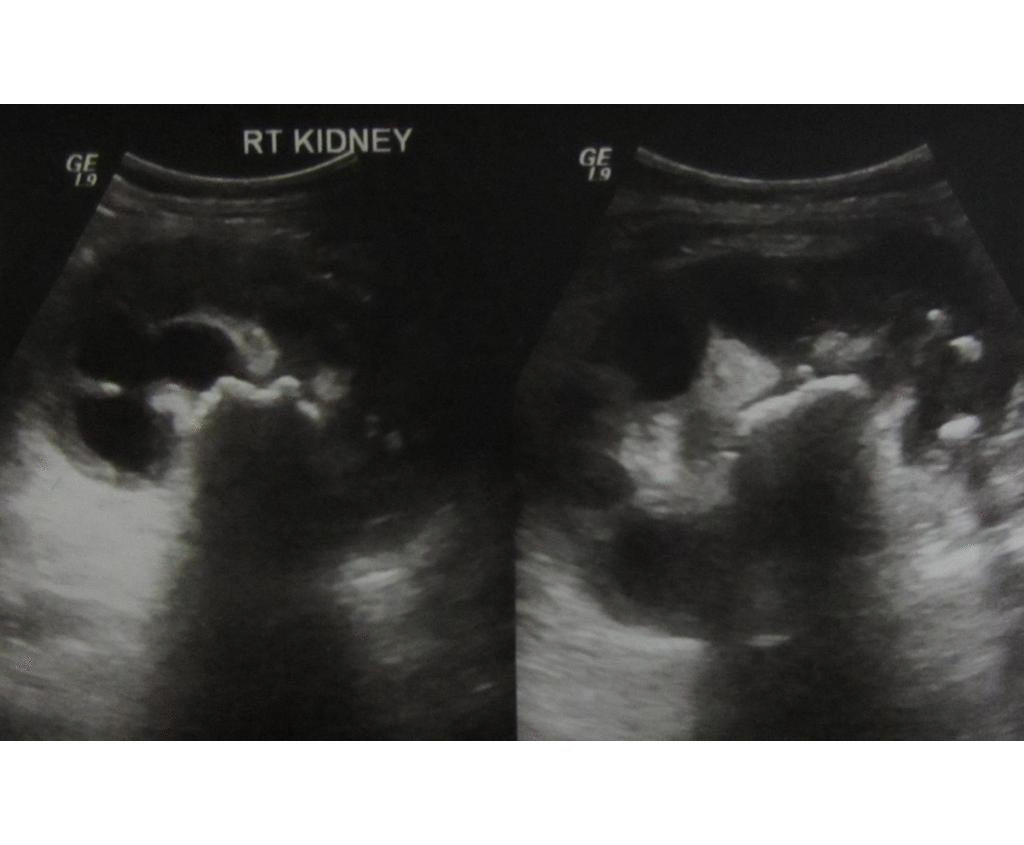

From www.youtube.com

ULTRASOUND PYELONEPHRITIS acute part 1 YouTube Pyel O Acute pyelonephritis is a bacterial infection causing renal inflammation and is one of the most common kidney diseases. Acute pyelonephritis is a sudden and severe kidney infection. It causes the kidneys to swell and may permanently damage them. Π υ ́ ε λ ο ς « bassin », entrant dans la constr. A combining form meaning “pelvis,” used in the. Pyel O.

From www.wikidoc.org

Pyelonephritis echocardiography and ultrasound wikidoc Pyel O Acute pyelonephritis is a sudden and severe kidney infection. Acute pyelonephritis is a bacterial infection of the kidney and renal pelvis and should be suspected in patients with flank pain and laboratory evidence. Retrouvez les explications sur les causes, les symptômes et les complications d'une pyélonéphrite. It causes the kidneys to swell and may permanently damage them. A combining form. Pyel O.